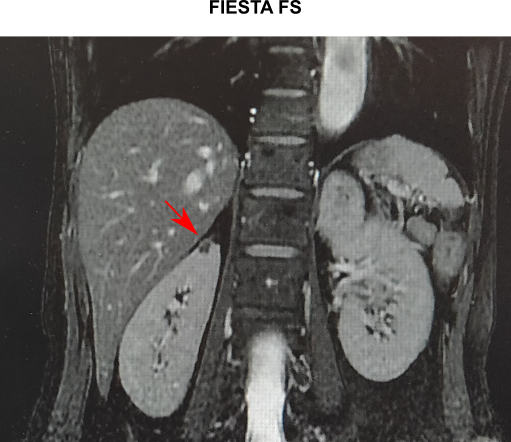

<‰ζ‘œŠŒ©

@E• •”’PƒMRIFtŒŒŠΗ‹Ψމ–bŽξ‹^‚’